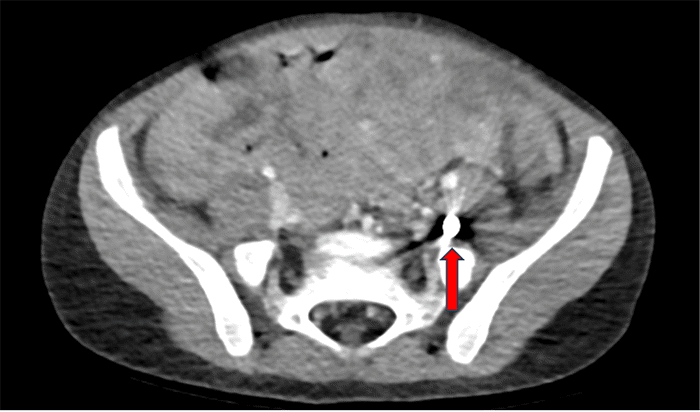

Given the patient’s stability and the localized nature of the injury, a CT scan was performed for further evaluation. Imaging studies were significant for retained foreign body lodged within the left psoas muscle (Figure 1). Additionally, the CT scan helped visualize the projectile’s trajectory from the anterior abdominal wall to the left psoas muscle. This trajectory confirmed a heightened suspicion for violation of the viscera. At this point, the decision was made to proceed with operative intervention due to the trajectory of the injury despite the absence of free air or free fluid in the radiographic interpretation.

Figure 1. Axial and Sagittal CT Abdomen & Pelvis. Published with Permission

(A) Axial view view of CT abdomen and pelvis showing the retained 9mm ballistic fragment

(B) Sagittal view of CT abdomen and pelvis showing the retained 9mm ballistic fragment